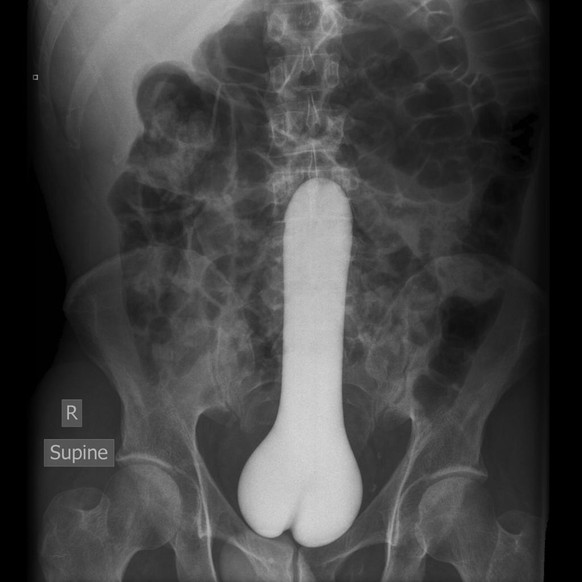

Ein Riesendildo

Bei dieser Aufnahme bleiben nicht viele Fragen offen. Es ist definitiv ein Riesendildo.

Die Aufnahme wurde mit der Bemerkung hochgeladen:

Diese Erklärung hätten wir in der Tat auch gerne gehört.